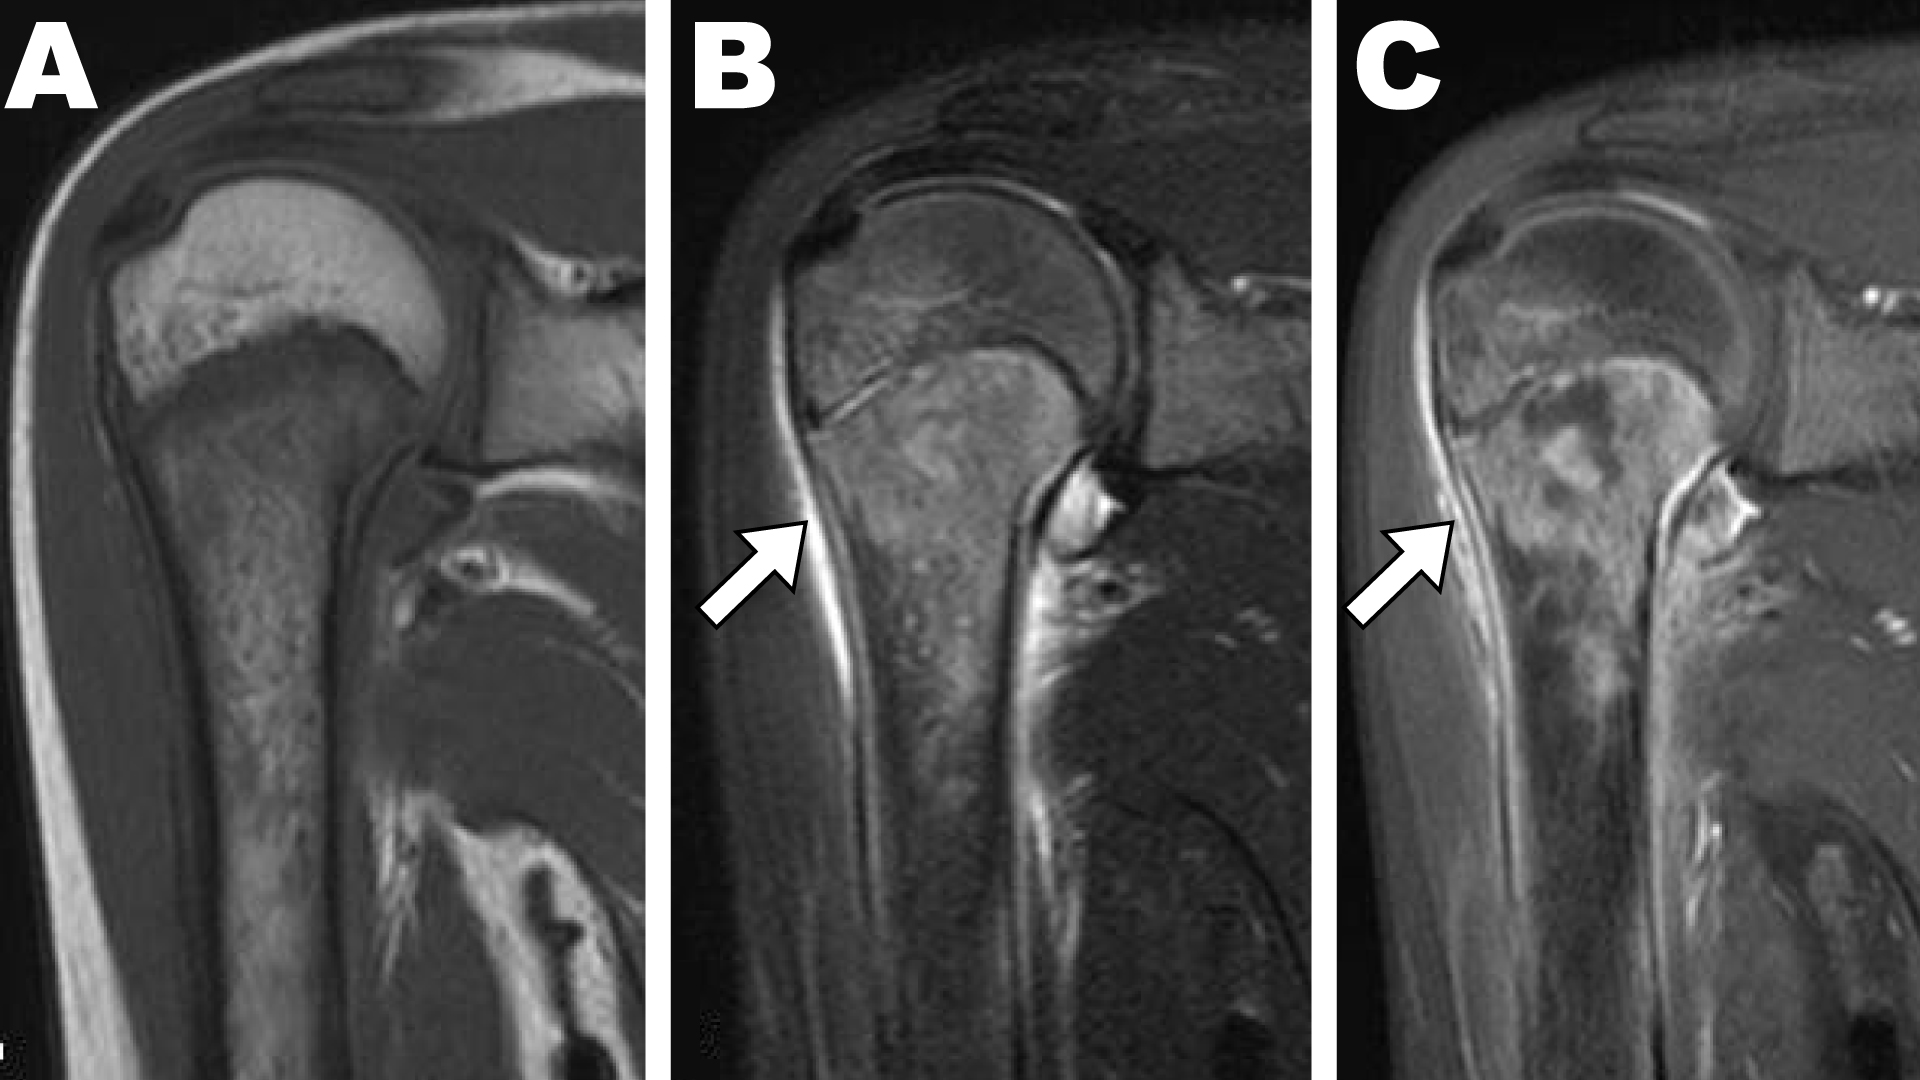

A previously healthy 9-year-old girl presented with a 3-day history of high fever (> 40 °C) and acute pain in the right shoulder. A blood chemical profile showed a C-reactive protein level of 9.7 mg per liter and a white cell count of 12,500 per cubic millimeter. Shoulder radiographs were normal, but magnetic resonance imaging showed acute osteomyelitis around proximal humeral epiphyseal plate and a subperiosteal abscess around the humeral neck (Figure 1). Vancomycin was empirically started after blood cultures taken. The blood cultures grew Methicillin-Susceptible Staphylococcus aureus (MSSA) and the antibiotherapy was de-escalated to cefazolin. After 1 week of parenteral antibiotics [1], she still had high fever and C-reactive protein level and white cell count were getting worse. Therefore, this therapy was considered ineffective and surgical management was required to control the infection [2]. A deltopectoral approach was used to drain the subperiosteal abscess, and resection was performed (Figure 2). The abscess cultures also revealed MSSA growth. Her shoulder pain and fever rapidly improved 2 days after surgery. At 2 weeks of surgery, blood chemical profiles were normal and blood cultures were negative. She recovered well and there has been no recurrence since a year.

Figure 1: Contrast-enhanced T1-weighted magnetic resonance imaging showed high signal intensity in the proximal humerus and a subperiosteal abscess (white arrow) around the medial humeral neck. T1-weighted (T1w) Turbo Spinecho Imaging (TSE) showed low signal intensity; (A) T2-weighted (T2w) TSE showed high signal intensity; (B) around proximal humeral epiphyseal plate. Contrast-enhanced T1w magnetic resonance imaging (C) T2w TSE showed high signal intensity around humeral neck (arrow).